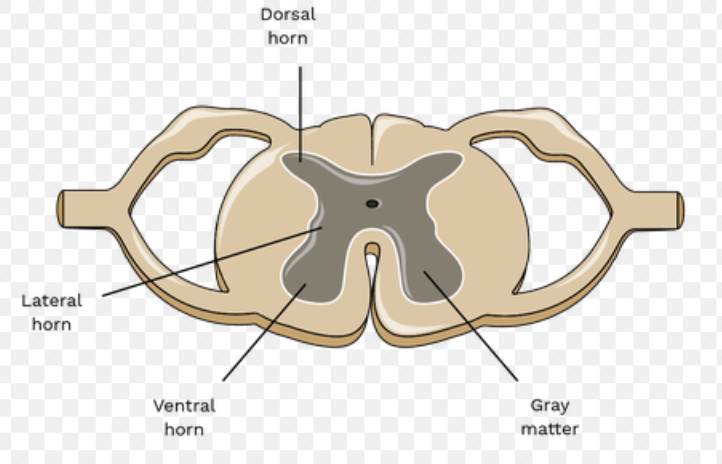

In the Spinal Cord, where is the Grey matter and White matter located

Grey matter is deep (inside), and White matter is superficial

Which spinal cord horns have nuclei associated with sensory information?

Posterior Gray horns

Which spinal cord horns have nuclei associated with motor information?

Anterior gray horns